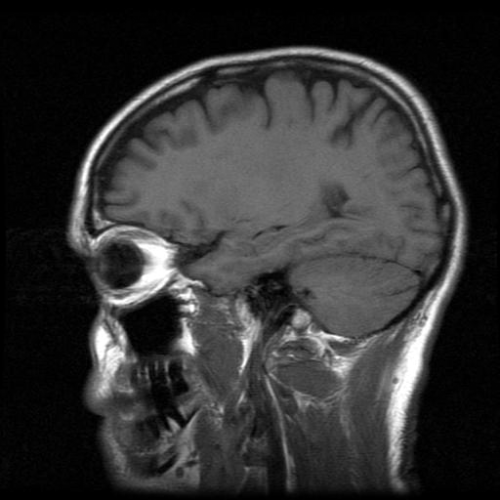

mri

Un recente studio, pubblicato sulla rivista medica New England Journal of Medicine ha descritto il modo con cui un gruppo di ricercatori britannici e belgi sono riusciti a comunicare con un paziente affetto da danno cerebrale, utilizzando la risonanza magnetica funzionale. Lo studio ha coinvolto gli scienziati del Medical Research Council (MRC), del Wolfson Brain Imaging Centre di Cambridge ed un team di ricercatori dell’Università di Liegi.

I pazienti in stato vegetativo sono svegli, non in coma, ma non hanno coscienza a causa dei gravi danni cerebrali subiti. Lo studio dimostra che le scansioni attuate con la risonanza magnetica sono in grado di permettere una comunicazione anche con quei pazienti quindi apparentemente tagliati fuori dal mondo.